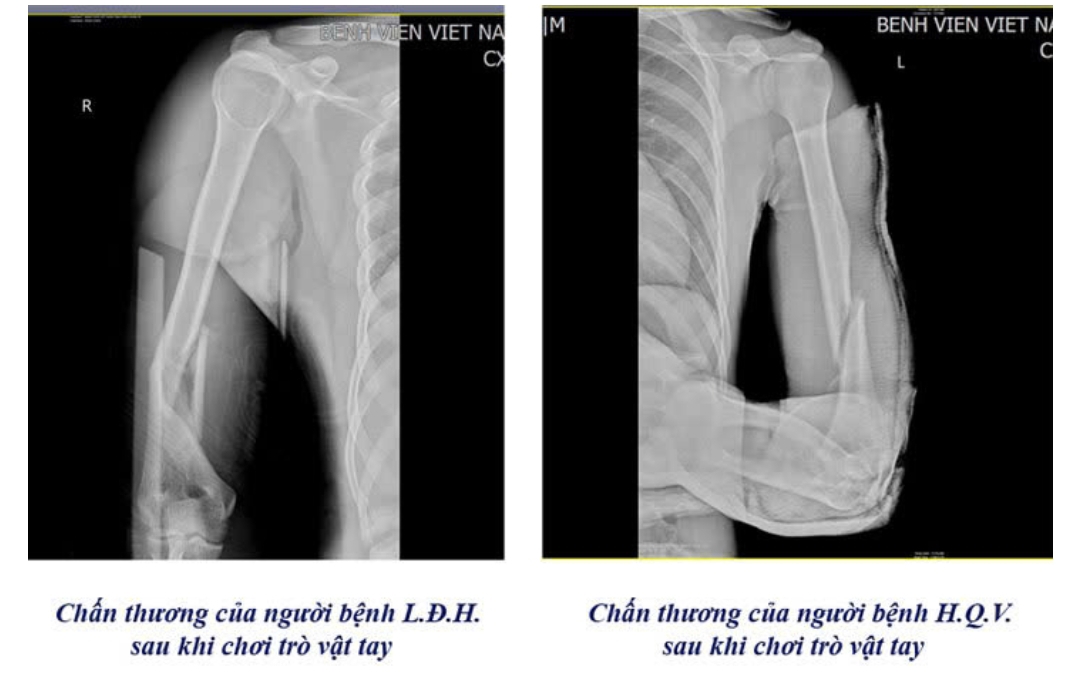

CẢNH BÁO NGUY HIỂM TỪ TRÒ CHƠI “VẬT TAY”

Bệnh viện Việt Nam Thụy Điển thời gian qua ghi nhận nhiều trường hợp học sinh, sinh viên nhập viện do gãy xương cánh tay khi tham gia trò vật tay. Theo bác sĩ Chấn thương Chỉnh hình & Bỏng, lực xoắn đột ngột trong lúc vật tay có thể khiến xương cánh tay gãy xoắn, thậm chí di lệch. Phần lớn bệnh nhân phải phẫu thuật kết hợp xương bằng nẹp vít để cố định và phục hồi.

Nhiều ca nhập viện trong tình trạng xương gãy phức tạp, gia tăng nguy cơ tổn thương dây thần kinh và mạch máu, để lại di chứng ảnh hưởng vận động về sau.